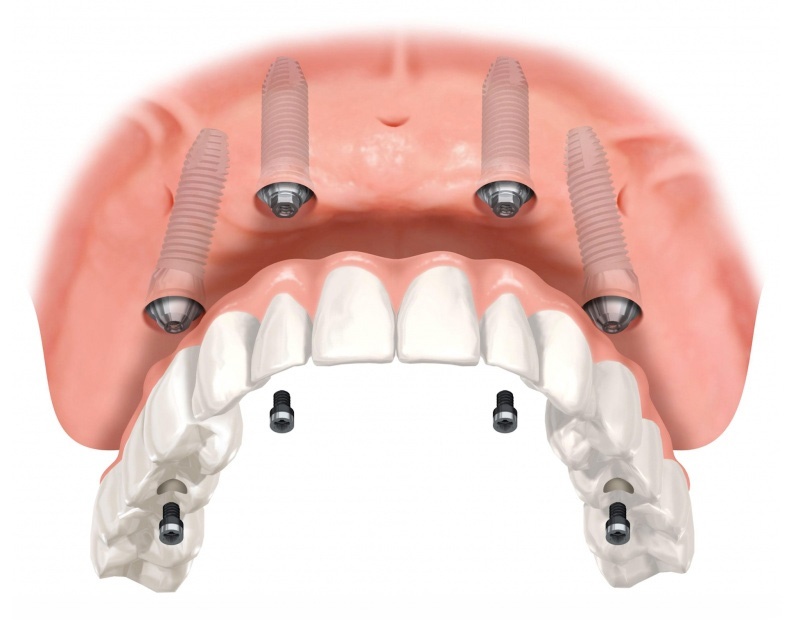

Bij deze patiënten zijn zygoma-implantaten vaak een echt goden-geschenk . Deze implantaten zijn daarom ook eerste keuze. Het ganse proces wordt gerealiseerd in drie tot vier dagen: van de plaatsing van de implantaten tot de plaatsing van de tijdelijke vaste brug in chroom-kobalt-hars met prachtige tanden. We kunnen dit uitvoeren zonder enig esthetische compromis. Raadpleeg voor meer informatie het hoofdstuk op mijn website over zygoma-implantaten.

- De heelkunde: we plaatsen de zygoma-implantaten en meestal ook enkele normale tandimplantaten. Vervolgens nemen we de afdruk.

- Deze afdrukken worden doorgestuurd naar het tandlabo met de opbouwinstructies.

- Twee dagen later plannen we een afspraak om de tanden met hun structuur te passen en te zien of alle parameters kloppen. Het pasmodel gaat vervolgens terug naar het labo met instructies voor laatste aanpassingen.